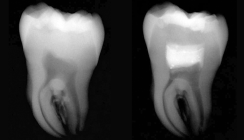

Zu Beginn sah die Behandlung nach einem Routineeingriff aus. Der Fall ist gleichzeitig jedoch auch eine Falle, welche Sie vielleicht auf dem Röntgenbild erkennen können (Abb. 1). Neben der mesialen Karies wurde die Amalgamfüllung gleichzeitig, aufgrund von Leakage bukkal, mit ausgetauscht (Abb. 2).

Nach drei und sechs Monaten erfolgten Kontrolltermine (Abb. 10 und 11), an beiden war die Patientin beschwerdefrei. Beim Sensitivitätstest mit Kälte war der Zahn stets negativ, was jedoch aufgrund der dicken Schichtstärke von MTA und Komposit nicht verwunderlich ist. Daher wurde zusätzlich noch ein elektrischer Pulpatest durchgeführt, der positiv war.